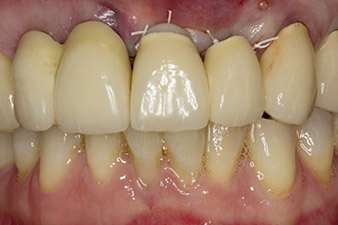

Después de la cicatrización primaria, los tejidos blandos se modelaron con ayuda del puente con base reconstruida. Dos meses después, se procedió a la exposición del área con una incisión de la cresta maxilar en sentido ligeramente palatino (figura 2).

En el caso clínico presentado, la situación se resolvió en la primera intervención con un implante en la posición 22, así como con otro en la posición de la pieza dental 23 extraída en el transcurso posterior. El segundo implante se realizó después de la osteointegración del implante 22. El puente remodelado se volvió a colocar hasta la cicatrización del implante 23 y la conformación para la prótesis definitiva. Las ventajas de este procedimiento escalonado son una capacidad de carga segura de los implantes y una buena maduración de los tejidos duros y blandos (5).